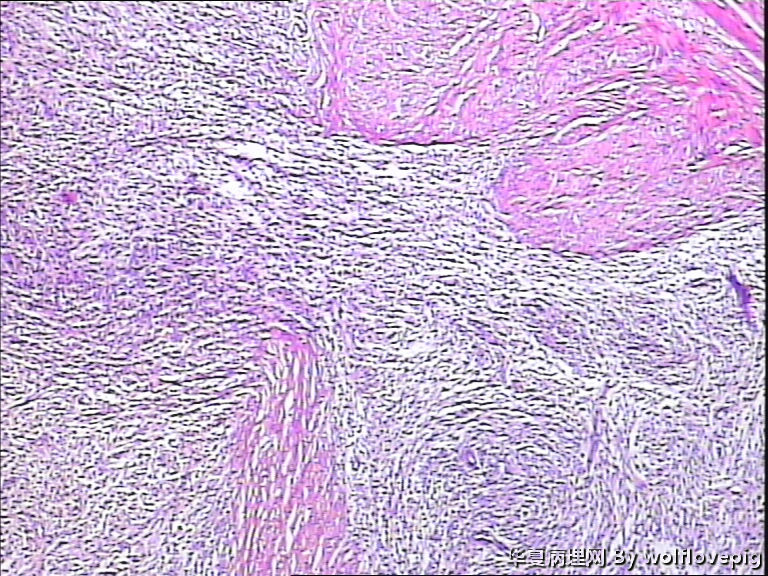

37y,肌壁间可见多个小结节0.2~0.8cm。

多发的间质结节,局部区域与肌壁交错,界限不是太清,要排除低级别间质肉瘤

123图感觉要考虑低级别内膜间质肉瘤,最好标记一下

间质细胞增生结节,要排除低级别间质肉瘤

考虑低级别子宫内膜间质肉瘤

多发结节,肿瘤边缘不甚规则,局部有浸润性现象,细胞有一定的异形形,出现核分裂,并见灶性坏死。